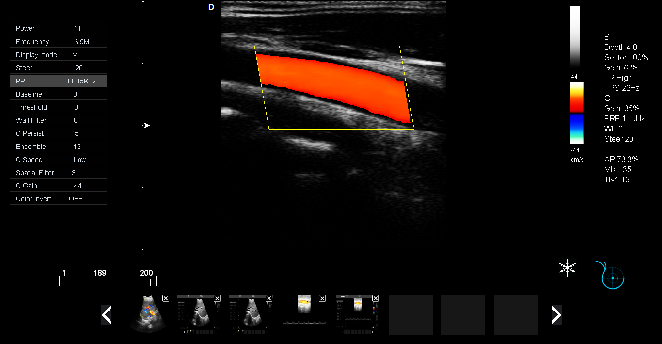

頸動脈血流:

頸動脈彩超是診斷、評估頸動脈壁病變的有效手段之一,在動脈粥樣硬化的流行病學調(diào)查和對動脈粥樣硬化預(yù)防、治療試驗的有效性評價中起著關(guān)鍵作用。

頸動脈彩超不僅能清晰顯示血管內(nèi)中膜是否增厚、有無斑塊形成、斑塊形成的部位、大小、是否有血管狹窄及狹窄程度、有無閉塞等詳細情況, 并能進行準確的測量及定位,還能對檢測動脈的血流動力學結(jié)果進行分析。